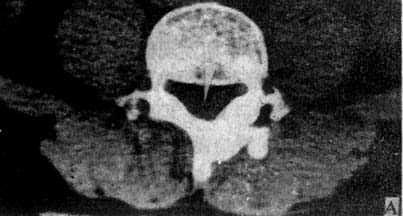

(二)脊柱横断面CT扫描 可见三个标准层面图像,即通过椎弓根、椎间孔和椎间盘的扫描层面。

1.椎弓根层面 由椎体、椎弓根、椎弓板和棘突围成一完整的骨环称为椎管(图5-1-5A)。正常椎管前后径为16~17mm,下限11.5mm;横径20~24mm,下限16mm。

图5-1-5 正常脊柱CT横断面扫描

A.椎弓根层面显示椎管由椎体、椎弓根和椎弓板围成的骨环,椎管中央为脊髓(→)